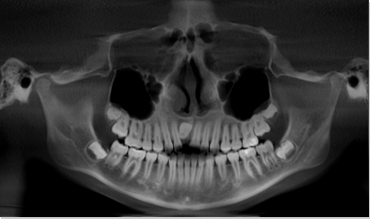

CBCT is a digital x-ray scanner specifically designed for scanning the head and jaws. The scanner rotates 360 degrees around the patient's head in a matter of seconds. The x-ray is a low energy fixed anode tube similarly used in panoramic machines. This method reduces radiation scatter common to most conventional x-rays. The cone shaped x-ray provides 360 views that can be presented in 2D image and 3D volume for advanced planning and diagnostic support.

This one scan provides more images than plain film conventional imaging, with complete visualization of the patient's entire maxillofacial region. These images clearly display TM disorders, impacted teeth, critical bone and tooth relationships, oral- nasal airways, para-nasal sinus, mandibular canal and difficult to see pathologies within one volume. The user friendly software system reconstructs true size, distortion free, high resolution images.

The CBCT scanner is fast, comfortable (nothing goes in the mouth), and painless for patients. It provides a complete set of maxillofacial images with less radiation than conventional orthodontic and medical type CT work-ups. CBCT now can re-create true size cephalometric and panoramic images, virtually eliminating the need for conventional orthodontic x-rays, so your patients will be comforted by the knowledge that you have all the information needed to evaluate and plan their treatment